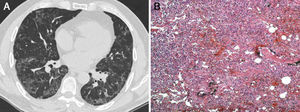

A continuación se repitió la TCAR de tórax, que mostró una borrosidad en vidrio esmerilado y una opacidad reticular periférica, que se apreciaba sobre todo en las bases pulmonares (fig. 1A).

A) TCAR de tórax en la que se observa una borrosidad en vidrio esmerilado y una opacidad reticular periférica que se manifiestan especialmente en las bases pulmonares. B) El examen histopatológico mostró lo siguiente: tabiques alveolares ensanchados con proliferación de neumocitos tipo ii e infiltrado inflamatorio mononuclear con fibrosis intersticial en un patrón en parches (patchwork pattern) que sugería una neumonía intersticial usual (tinción de hematoxilina-eosina, aumentos originales 100×).

El examen histopatológico mostró lo siguiente: tabiques alveolares ensanchados con proliferación de neumocitos tipo II e infiltrado inflamatorio mononuclear con fibrosis intersticial en un patrón parcheado (patchwork pattern) que sugería una neumonía intersticial usual (fig. 1B). El periodo postoperatorio transcurrió sin incidencias y el paciente fue remitido a la unidad de neumología para un tratamiento médico adecuado.